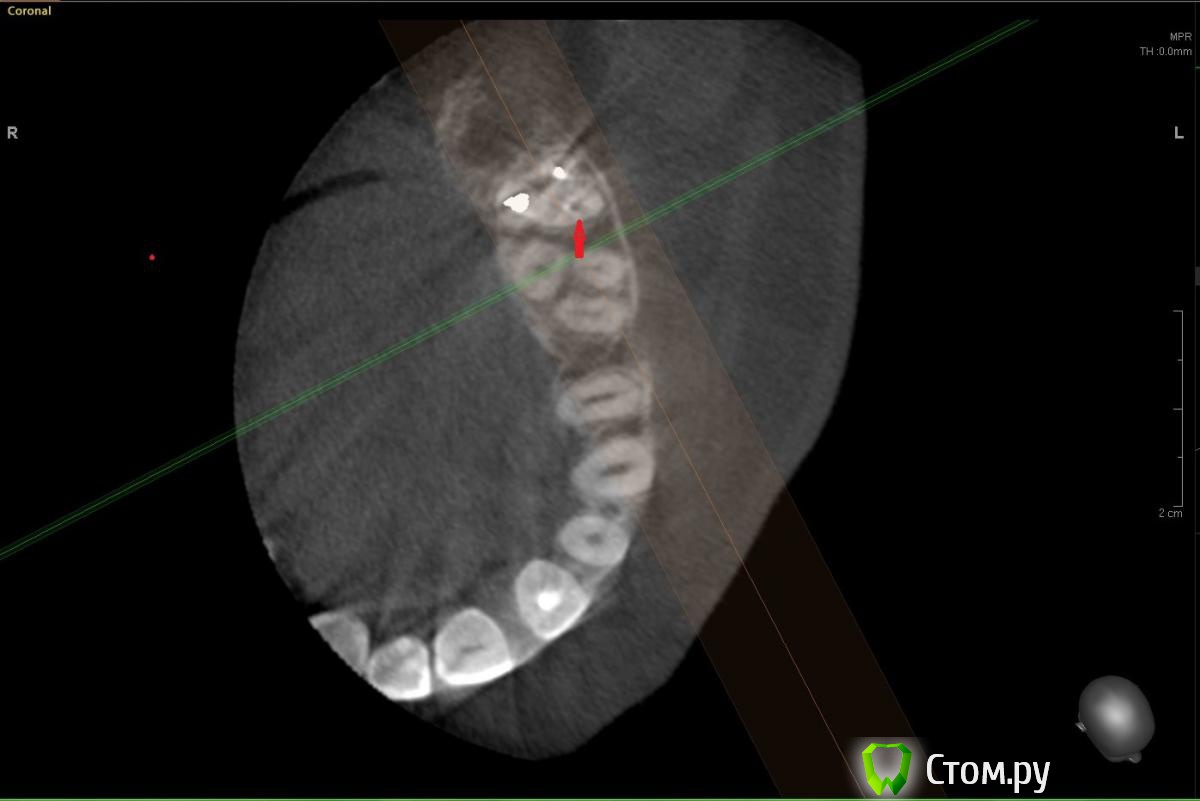

Еще один прицельный снимок этого зуба. Есть вариант того, что там пропущен канал?[/url]

Сначала предположила что есть пропущенный канал исходя из этого:

Но оказалось, что это как бы "пора"